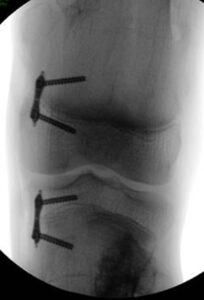

These deformities can be corrected with various techniques:

- osteotomies

- hemi-epiphysiodesis

- lengthening with axis correction

Exostoses: surgery to correct heterometry

By the same mechanisms, patients with multiple exostotic disease may present length differences (LLD) of the upper and lower limbs or relative length differences between the forearm bones.

- hemi-epiphysiodesis to slow the growth of the longer limb

- lengthening of shortened bone segments